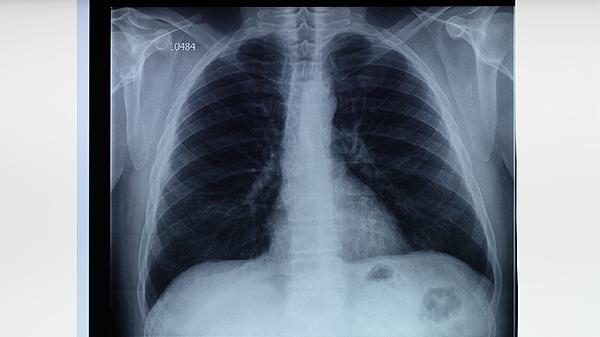

原發(fā)性肺結核典型表現為原發(fā)綜合征三聯征,包括肺內原發(fā)病灶、淋巴管炎和肺門淋巴結腫大。肺結核的病理表現更為多樣,繼發(fā)性肺結核常見浸潤性病變、空洞形成或纖維鈣化灶。

原發(fā)性肺結核在X線胸片上多顯示為啞鈴狀陰影,即原發(fā)灶-淋巴管炎-淋巴結炎的典型組合。肺結核的影像學表現因類型而異,繼發(fā)性肺結核常見上葉尖后段或下葉背段的斑片狀、云霧狀陰影。